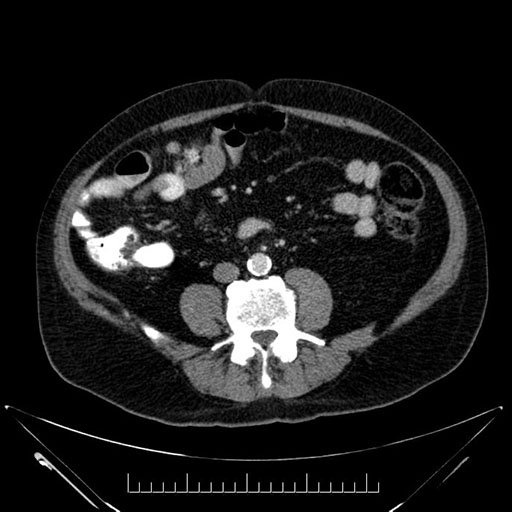

Imaging Analysis

Look through the patient's CT scan to identify any areas of concern for the necessary procedure.

Based on your CT findings, which issue(s) would give reason for "planned slowing down moment(s)" in this case?